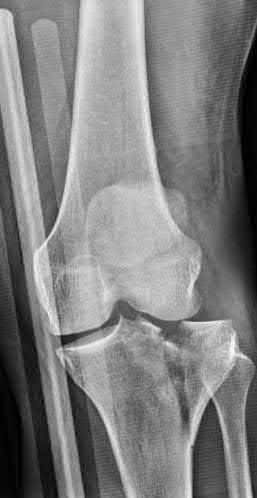

A 32-year-old woman presents with persistent knee pain. Imaging reveals an eccentric, lytic epiphyseal lesion extending to the subchondral bone, characteristic of a giant cell tumor of bone. She is prescribed denosumab prior to surgical intervention. What is the precise mechanism of action of this medication?

Denosumab is a human monoclonal antibody that binds specifically to RANKL (Receptor Activator of Nuclear factor Kappa-B Ligand), a protein essential for the formation, function, and survival of osteoclasts. By neutralizing RANKL, denosumab prevents it from binding to the RANK receptor on osteoclast precursors, dramatically decreasing osteoclast-mediated bone destruction, which is the primary pathology in Giant Cell Tumor of Bone.